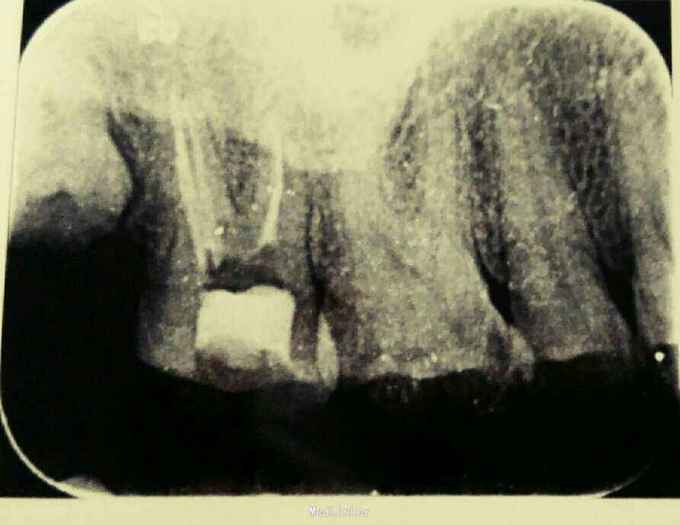

诊断:17牙髓炎 治疗计划:17根管治疗术 处置:17开髓,揭顶,见少量渗出,探及MB、DB、P三个根管口,P疏通过程疼痛明显,干燥,置失活剂,氧化锌暂封 一周后复诊:主诉无不适,氧化锌暂封完整在位,去除氧化锌,清理髓腔,测量根管长度,MB=P=19mm,DB=21mm,根管锉扩大至MB、DB25#,P至35#,双氧水、生理盐水交替冲洗,干燥根管,髓腔置CP棉球,氧化锌暂封 一周后复诊:无不适,氧化锌暂封在位,去除暂封,试主尖,冷侧牙充填,根尖片显示:恰填。 一周后复诊:无不适,叩-,患者因经济原因拒绝修复治疗,去除暂封后,磷酸锌垫底,树脂充填,调合,磨光。

讨论:患者就诊时,有自发痛、夜间痛病史,后来疼痛程度降低,是牙髓部分坏死的表现,开髓过程中无明显疼痛,说明冠髓已经坏死,但是腭侧根管探痛明显,仍为活髓,渗出量不大,所以首次封失活剂。常规预备根管后,冷侧压充填,建议患者全冠修复,患者拒绝,树脂充填后予以充分降低咬合,并嘱咐患者不要用患牙咀嚼坚硬食物。